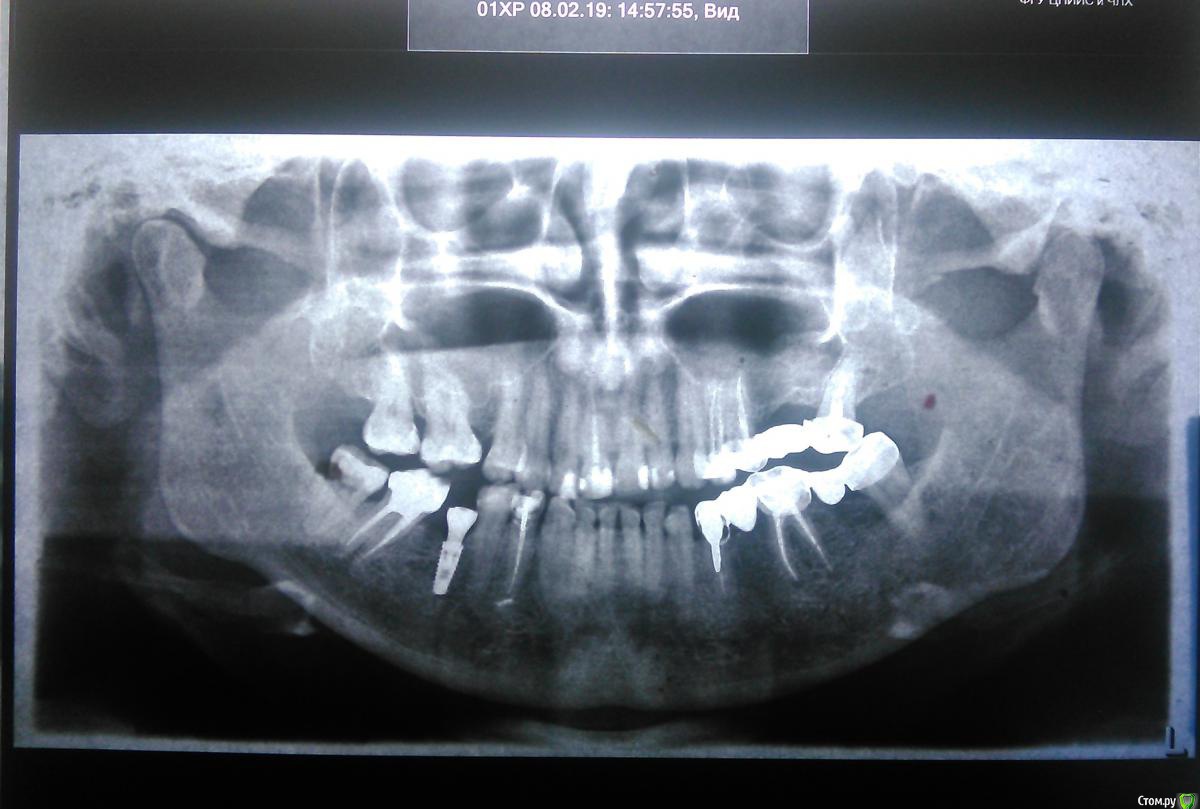

Добрый день, уважаемые специалисты. Нуждаюсь в Вашем совете. Вкратце он звучит так: предстоит обновление зубного моста, вставка импланта, при этом прикус хотелось бы тоже подровнять, но знаний крайне мало,-  стоит ли, кто это делает, какого хорошего врача посоветуете, каков алгоритм, и плюсы и минусы такого большого моего вмешательства в жизнь своей челюсти. Подскажите пожалуйста из вашего опыта, как лучше бы мне поступить.

А подробности вот: 40 лет, зубы хрупкие изначально, не болят особенно, но просто скалываются при нагрузке со временем. Прикус с детства неправильный (несколько раз слышала об этом), но видимо, не сильно неправильный, ибо вопрос о брекетах или о чем-то серьезном не стоял. После школьных лет системного лечения из-за частых переездов почти не было, и в итоге 10 лет назад пришлось ставить мост на левую часть челюсти,- на верхний и нижний ряд зубов одновременно. В это же время и справа был рекомендован мост(одновременно и снизу и сверху зуба нет), но из-за него пришлось бы лишать нервов несколько соседних зубов, решили оставить как есть. И за эти 10 лет вид мой (как по мне) сильно изменился не только от возраста, а еще из-за несимметричной нагрузки. Но вид- это еще что, - кажется, и дышать сложнее становится со временем, осанка меняется. Стоит подвигать челюстью вперед- дышится свободней заметно носом, но в висках иногда, редко подбаливает после этого, или независимо от этого.

P.S. фотографии мои не очень получились, задачка особенно,- чтоб справа и слева все зубы были видны)) , но я старалась)). если все же нужно что-то дофотографировать или сделать 3d, - то все к тому идет, готова сделать, подъехать на консультацию и т.д.